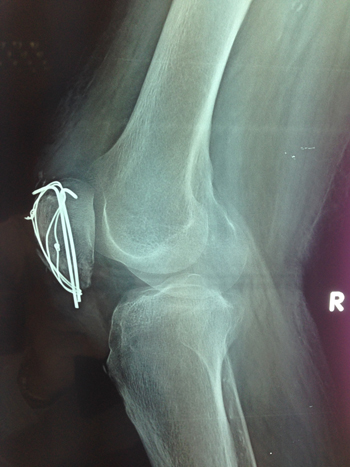

| Κάταγμα επιγονατίδος |